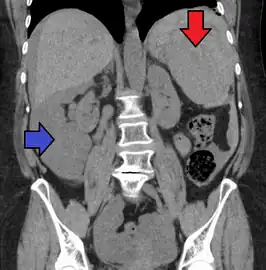

Image of abdomen shows ruptured spleen (and the perisplenic hematoma)

Splenic rupture is usually evaluated by FAST ultrasound of the abdomen.[3] Generally this is not specific to splenic injury; however, it is useful to determine the presence of free floating blood in the peritoneum.[3] A diagnostic peritoneal lavage, while not ideal, may be used to evaluate the presence of internal bleeding a person who is hemodynamically unstable.[4] The FAST exam typically serves to evaluate the need to perform a CT scan.[4] Computed tomography with IV contrast is the preferred imaging study as it can provide high quality images of the full peritoneal cavity.[3]